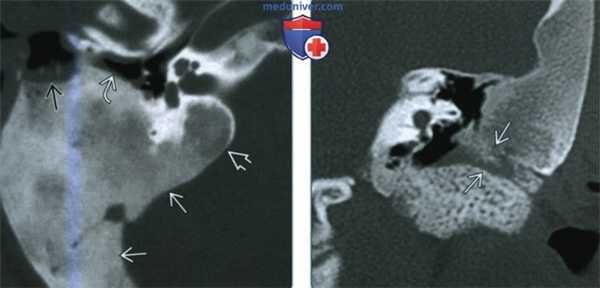

(Слева) При аксиальной КТ в костном окне определяется фиброзная дисплазия (ФД) склеротического типа, с поражением сосцевидного отростка и внутреннего уха и обрастанием задних отделов среднего уха. Экспансивный характер ФД приводит к стенозу наружного слухового канала (НСК). Обратите внимание на область ранее выполненной биопсии спереди и снаружи.

(Справа) При корональной КТ в костном окне определяется склеротическая ФД, приводящая к окклюзии НСК. Можно предположить наличие клинически значимой кондуктивной тугоухости. При отоскопии определяются изменения, схожие с врожденной мальформацией ИСК.2. КТ при фиброзной дисплазии височной кости:

(Слева) При аксиальной КТ в передних отделах левой височной кости определяются очаги кистозной ФД, выглядящие агрессивными. Определяется также нежное «матовое стекло». Обратите внимание на визуализирующийся лабиринтный сегмент канала лицевого нерва и поражение ямки коленчатого ганглия.

(Справа) При аксиальной КТ в костном окне определяется полиостотическая фиброзная дисплазия с поражением обеих височных костей. Хорошо видны другие множеавенные очаги, в т.ч. в затылочной кости справа, в скате, клиновидной и лобной кости.в) Дифференциальная диагностика фиброзной дисплазии височной кости: